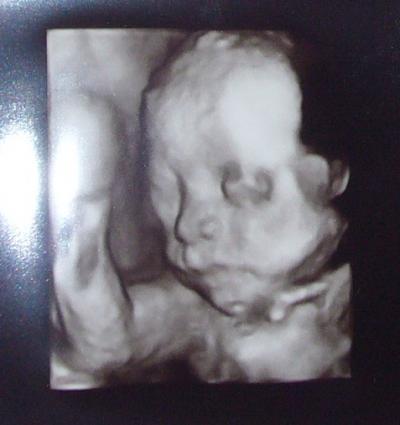

Hallo ihr Lieben Hab ja schon geschrieben, dass ich zur Feindiagnostik musste, weil die Nieren von meinem Kleinen gestaut sind. Gestern wars dann soweit, aber alles ist in bester Ordnung! Sind sogar etwas zurückgegangen in der Größe die Nieren Und ich hab (kostenlos!) sogar drei Bildchen vom 3D-Ultraschall bekommen. Eins will ich euch mal zeigen. Er hat 1:1 meine Nase und meine Wangenknochen!

Bild zu Zurück von der FD wegen Nierenstau (mit Bild) - Forum für September - Mamis